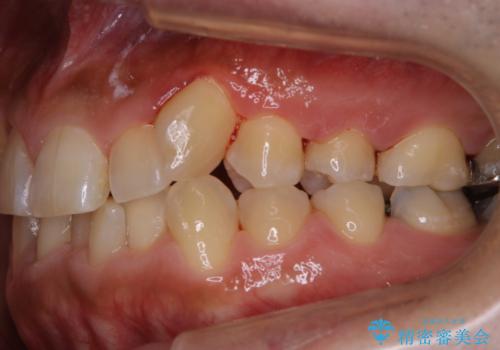

前歯メインにステインの付着が見られ、コース内容を相談した結果PMTC(保険外治療)の30分コースを行いました。